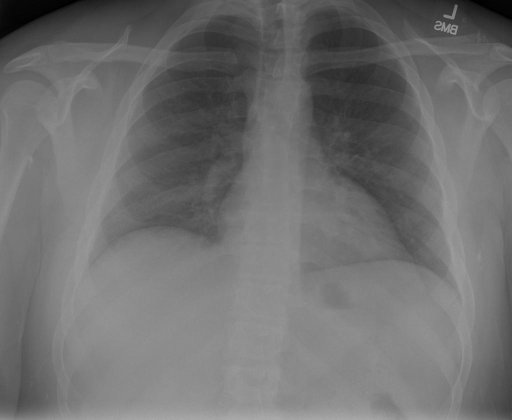

*以下效果来自于**低质量**的数据训练和权重

影像诊断:

|X光影像|诊疗报告(医生)|XrayGLM|

|:-|:-|:-|

||根据X射线图像,心脏大小正常,肺部看起来很清晰。已经排除了肺炎、积液、水肿、气胸、腺病、结节或肿块的存在。该发现表明一切正常。换句话说,总体印象是胸部正常。|X光片显示,心脏大小正常。肺部没有气胸或胸腔积液的证据。骨骼结构看起来没有任何异常。总的来说,X光片表明没有发现急性心肺疾病的迹象。|

||X光图片显示没有扭曲的区域、可疑的骨质不透明度或胸腺积液。心脏大小轻微增大,但非常稳定。此外,没有气胸的证据,肺野也正常。总体来说,X光片显示没有急性心脏异常,但要注意轻微的心脏扩大。|X光片显示,心脏大小正常。肺部和纵隔轮廓清晰,没有气胸或胸腔积液的证据。骨骼结构完整,没有任何急性异常。|

||心影形态在正常范围内。没有急性骨质异常。有可能出现没有明显的吸水或肺实质状况的线索。没有大面积积液或气胸。有可能怀疑其有误吸或肺实质问题。为了确诊和治疗,可能需要进行适当的影像学随访。|心脏大小正常,肺部和纵隔轮廓清晰。没有急性异常或活动受限的证据。没有任何明显的气胸、胸腔积液或肺不张的迹象。此外,也没有发现任何局灶性骨质异常或其他急性疾病。|